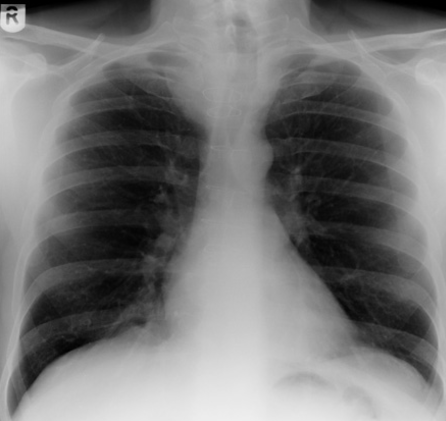

sarcoidosis

BHL